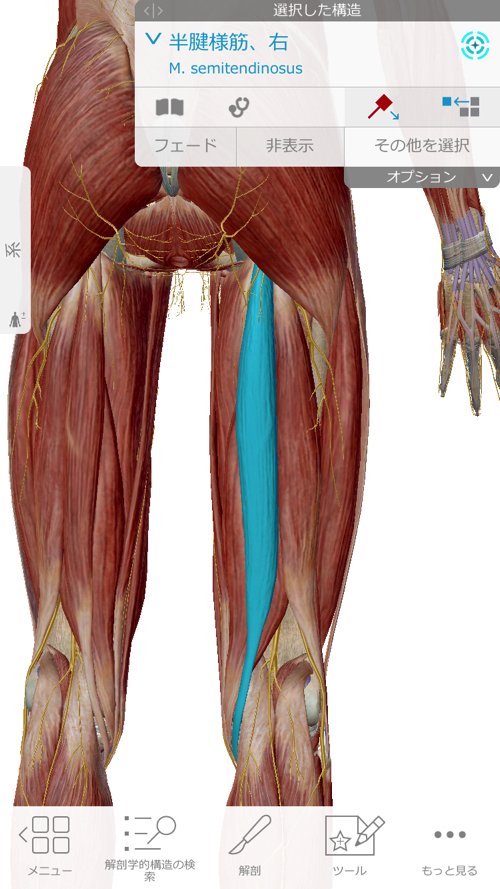

そしてもう1つは太腿の硬直でした。

そして太腿関連の施術

左足の太腿にも痛みが出ていました。